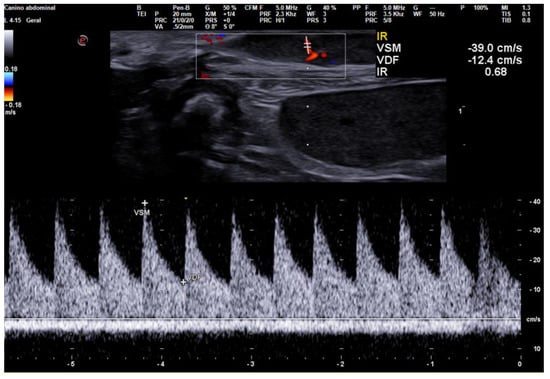

3.2. Doppler Ultrasonography

- Soler, M.; Dominguez, E.; Lucas, X.; Novellas, R.; Gomes-Coelho, K.V.; Espada, Y.; Agut, A. Comparison between ultrasonographic findings of benign and malignant canine mammary gland tumours using B-mode, colour Doppler, power Doppler and spectral Doppler. Res. Vet. Sci. 2016, 107, 141–146. [Google Scholar] [CrossRef]

- Feliciano, M.A.R.; Vicente, W.R.R.; Silva, M.A.M. Conventional and Doppler ultrasound for the differentiation of benign and malignant canine mammary tumours. J. Small Anim. Pract. 2012, 53, 332–337. [Google Scholar] [CrossRef]

- Navarro, D.M.; Silva, D.M.F.; Costa, F.S.; Wischral, A. Dopplerfluxometric and angiogenic analysis of canine mammary tumors. Arq. Bras. Med. Vet. 2018, 70, 1099–1108. [Google Scholar] [CrossRef]